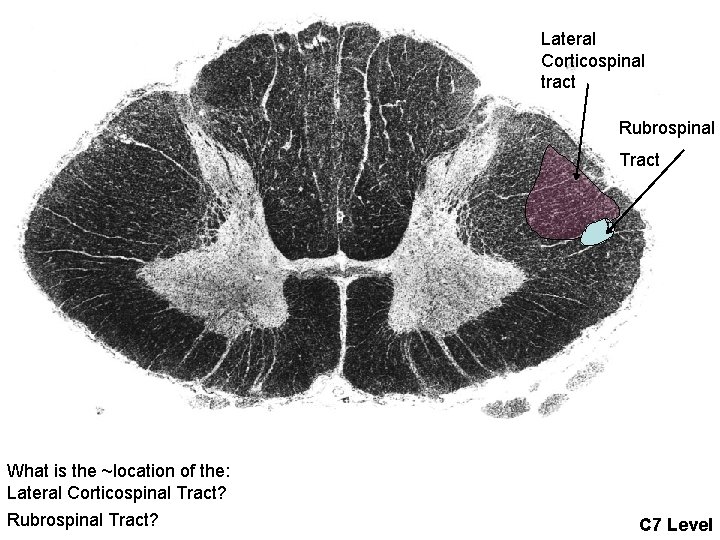

Lateral Corticospinal tract Rubrospinal Tract What is the ~location of the: Lateral Corticospinal Tract? Rubrospinal Tract? C 7 Level